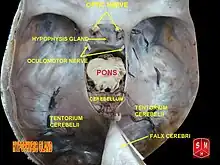

L'hypophyse se trouve dans une cavité osseuse, la fosse hypophysaire qui se situe dans l'os sphénoïde. Elle est protégée par la selle turcique. Elle est reliée à une autre partie du cerveau appelée l'hypothalamus par une tige hypophysaire (également appelée tige pituitaire). Elle produit des hormones qui gèrent une large gamme de fonctions corporelles, dont les hormones trophiques qui stimulent les autres glandes endocrines. Cette fonction lui a valu de se faire appeler par les scientifiques « glande maîtresse » du corps, mais aujourd'hui on sait que l'hypophyse est régulée par les hormones (neuro-hormones) émises par l'hypothalamus.

Anatomie

L'hypophyse est divisée en deux lobes : l'antéhypophyse (adénohypophyse) en avant, et la posthypophyse (neurohypophyse) en arrière. L'adénohypophyse dérive du plafond de la cavité buccale primitive (stomodeum), tandis que la neurohypophyse est une extension de l'hypothalamus, relié à celui-ci par la tige pituitaire, et contient les axones de neurones dont les corps cellulaires se trouvent dans l'hypothalamus. On peut également trouver entre l'antéhypophyse et la posthypophyse, une troisième structure, l'hypophyse intermédiaire, bien développée chez certaines espèces animales[Lesquelles ?] : chez l'humain, l'hypophyse intermédiaire (pars intermedia) est seulement visible en période fœtale et jusqu'à l'âge de dix ou vingt ans ; chez l'adulte, il subsiste quelques structures kystiques (follicules, restes de la poche de Rathke), ainsi qu'un infiltrat chromatophile basophile.